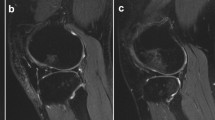

Preoperative MRI scans were analysed on a picture archiving and communicating system (PACS) workstation and reviewed for the presence of displaced posterolateral TPIF by two observers (one senior orthopaedic resident and one fellowship-trained musculoskeletal radiologist), blinded to clinical data. MRI signal change at the posterolateral tibial plateau was classified as impaction fracture only if there was a displacement of subchondral or cortical bone at the posterolateral tibial plateau rim visible on sagittal MRI T1-weighted images, according to Bernholt et al. [1]. TPIFs were graded into type I fractures when the articular surface was not involved (Fig. 2), type IIA with articular surface involvement and bone loss of less than 10% of the tibial plateau, and type IIB with more than 10% bone loss [1]. Type III fractures were defined as impaction fractures resulting in a displaced bony fragment, subclassified into type IIIA with a shear fragment and type IIIB with a depressed fragment (Fig. 3) [1]. For this study, type 0 and I TPIF were classified as low-grade, and type II or above as high-grade.

Magnetic resonance imaging of the left knee joint of a 24-year-old patient after ACL injury. The sagittal proton-density weighted image (A) shows a posterolateral tibial plateau fracture not involving the articular surface with a small cortical buckle (arrow in A), corresponding to a Type I fracture. The coronal T2-weighted fat-suppressed image (B) shows hyperintense signal alteration with intact fibres of the distal anterolateral complex (arrow in B), consistent with a low-grade injury